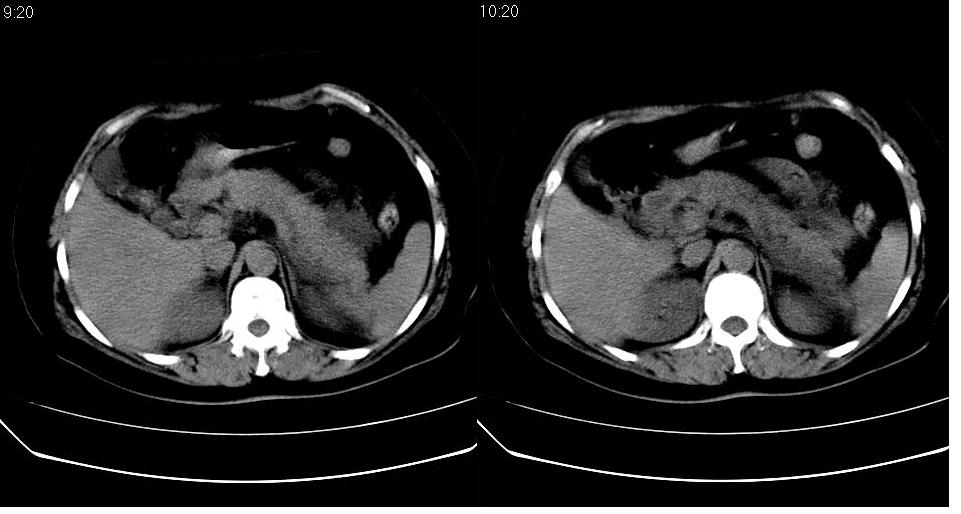

女 52岁,腹痛两天,无其它不适。

慢性胆囊炎,胆囊结石,胆源性胰腺炎考虑假囊肿形成。

胆囊、胆总管结石,胰腺炎,少量腹水。

左肾周筋膜增厚,肾前间隙积液,胰腺肿大,胆囊结石,胰腺炎

胆囊结石 胰腺炎伴胰尾假性囊肿形成.

1、慢性胆囊炎,胆囊结石、胆总管结石。诊断依据:胆囊内、胆总管内见高密度影,胆囊已有萎缩,说明时间已较长,胆囊壁有增厚。

2、胆源性胰腺炎,诊断依据:同1外+左肾周筋膜增厚,肾前间隙积液,胰腺肿大。